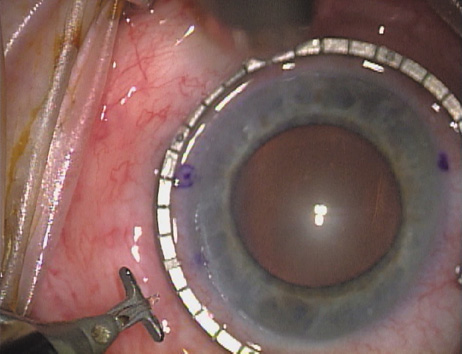

ways. Our preferred method makes use of a modified Fine-Thornton fixation

ring (Nichamin Fixation Ring and Gauge; Mastel Precision, Storz, Rhein

Medical). This instrument serves to fixate and position

the globe in order to optimize incision placement, as well as to delineate

the extent of arc to be incised. One visually extrapolates from

the limbus to marks on the surface of the ring. Each incremental mark

is 10 degrees apart, and bold hash marks (180 degrees) opposite

to each other serve to align and center the incision over the steep

meridian. This approach obviates the need to ink and physically mark

the cornea. If one desires, particularly when first gaining experience

with LRIs, a two-cut RK marker may be used to place ink marks upon the

cornea to show the exact extent of arc that is to be incised, in conjunction

with the fixation ring/gauge (Fig. 4). Alternatively, various press-on markers are available, such as

markers, rings, and blades for performing LRIs.  Fig. 4. The Nichamin Fixation Ring and Gauge serves to both fixate the globe and

delineate the extent of arc to be incised; a two-cut radial marker may

be used to mark the extent of arc to be incised, and the Mastel Nichamin

Force AK Diamond Blade with preset depth of 600 microns. Fig. 4. The Nichamin Fixation Ring and Gauge serves to both fixate the globe and

delineate the extent of arc to be incised; a two-cut radial marker may

be used to mark the extent of arc to be incised, and the Mastel Nichamin

Force AK Diamond Blade with preset depth of 600 microns.